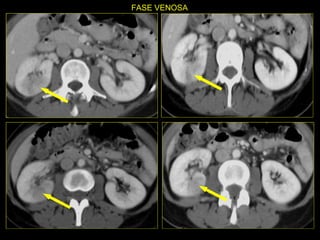

Caso # 5 ♀ ,  5ta década de la vida Antecedente de cirrosis hepática, hepatitis C y  Diabetes Mellitus. Ingresa con dolor abdominal por lo que se realiza estudio de TC en cortes axiales y coronales, fases arterial y venosa.

FASE ARTERIAL FASE VENOSA

Hallazgos Caso # 5 Área hipodensa en tercio medio del riñón izquierdo, sugestiva de lesión neoplásica a descartar área de inflamación focal.

SE INICIA ANTIBIOTICOTERAPIA Y SE INDICA ESTUDIO DE CONTROL A LOS 5  MESES.

Hallazgos estudio de control Caso # 5: La lesión ha desaparecido, lo que fue indicativo de que  se trataba de proceso inflamatorio focal resuelto posterior a manejo medico.